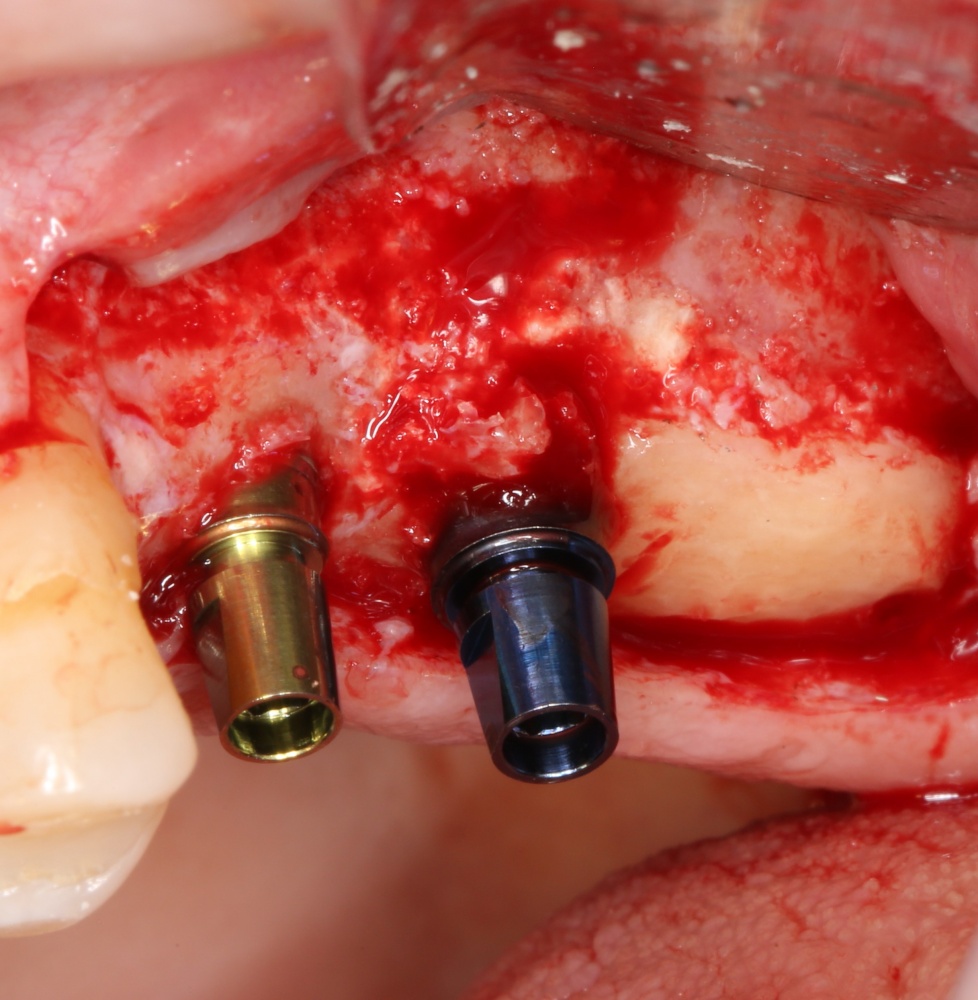

Устанавливаем формирователи десневой манжеты. Сегодня я называю эту процедуру не менее важной, чем любой другой этап имплантологического лечения:

И швы. Просто швы. Никаких дополнительных процедур.

Если честно, то сейчас бы я использовал другой шовный материал и другой тип швов. Одно неизменно, — и я об этом много раз говорил, — самая широкая часть формирователя десны должна находиться на уровне десны. Так, чтобы эффективно отрабатывать т. н. «биологическую ширину».